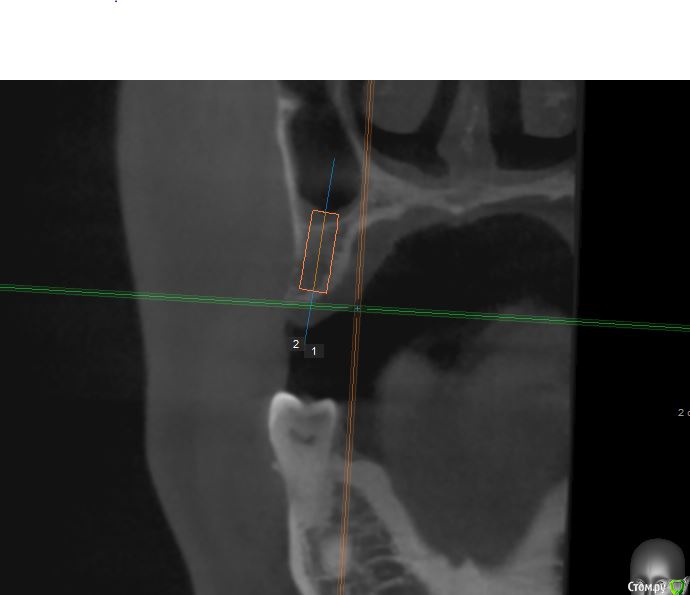

jm3300 Опубликовано 12 июля, 2016 Автор Поделиться Опубликовано 12 июля, 2016 А до операции КТ могли бы выложить? И сколько времени отсутствовали зубы в этой области?отсутствовали достаточно долги. КТ до: Ссылка на комментарий

jm3300 Опубликовано 14 июля, 2016 Автор Поделиться Опубликовано 14 июля, 2016 выкладываю кт Ссылка на комментарий

умножающий печаль Опубликовано 14 июля, 2016 Поделиться Опубликовано 14 июля, 2016 Промыть пазуху через соустье, курсом. Я отправляю к ЛОРам. Антибиотикотерапия, гипосенсибилизация. Один из винтов вестибулярно без костной поддержки, на мой взгляд. 1 Ссылка на комментарий

red_butler Опубликовано 15 июля, 2016 Поделиться Опубликовано 15 июля, 2016 гайморит всё таки есть?Не увидел, один винт похоже на выход 1 Ссылка на комментарий

red_butler Опубликовано 15 июля, 2016 Поделиться Опубликовано 15 июля, 2016 Пазуха чистая, Антон, какой винт на выход не понял?Может у пац аллергия ?На последних срезах, вестибулярно на 2/3 кости нет.Какая уж аллергия, если боль и отек 1 Ссылка на комментарий

умножающий печаль Опубликовано 15 июля, 2016 Поделиться Опубликовано 15 июля, 2016 Тоже не понял, вроде все хорошо стоят. Главное слизистые то в покое.Это пока в покое. Винт не покрытый костью, долго под мягкими тканями оставаться не будет. Неизбежна рецессия со всеми вытекающими. 1 Ссылка на комментарий